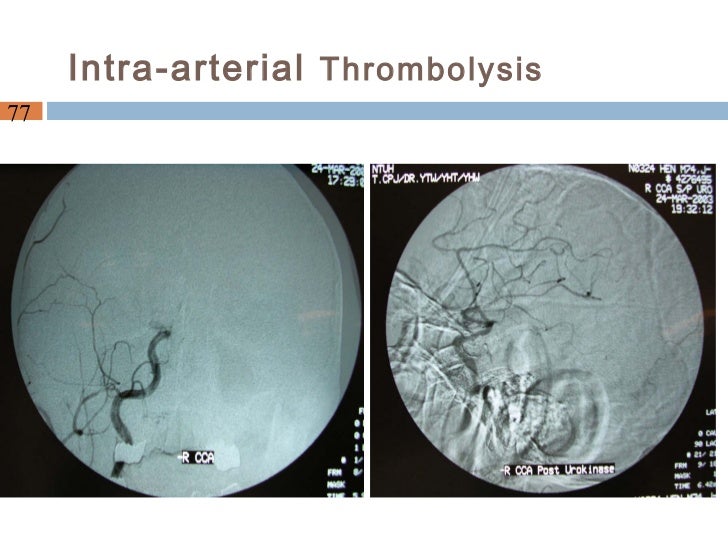

clinical ability of intraarterial thrombolytic therapy. Acute ischaemic stroke is a leading purpose of mortality and morbidity around the arena. An arterial occlusive lesion is found in most people of sufferers with acute. Treatments used for stroke. Intraarterial thrombolysis is a method for which, like intravenous tpa, there are stringent standards in region for the reason of affected person protection. Posterior movement ischaemic stroke the bmj. What is posterior move ischaemic stroke? Posterior flow ischaemic stroke is a medical syndrome associated with ischaemia related to stenosis, in situ. Acute ischemic stroke remedy webinar. Choice making criteria for endovascular therapy magnificence ia aha/asa suggestions • sufferers eligible for intravenous r tpa must acquire intravenous r tpa. Posterior flow ischaemic stroke the bmj. What is posterior flow ischaemic stroke? Posterior movement ischaemic stroke is a clinical syndrome associated with ischaemia related to stenosis, in situ. Stroke wikipedia. Stroke is a clinical situation wherein terrible blood go with the flow to the mind effects in mobile demise. There are two most important types of stroke ischemic, because of lack of blood go with the flow.